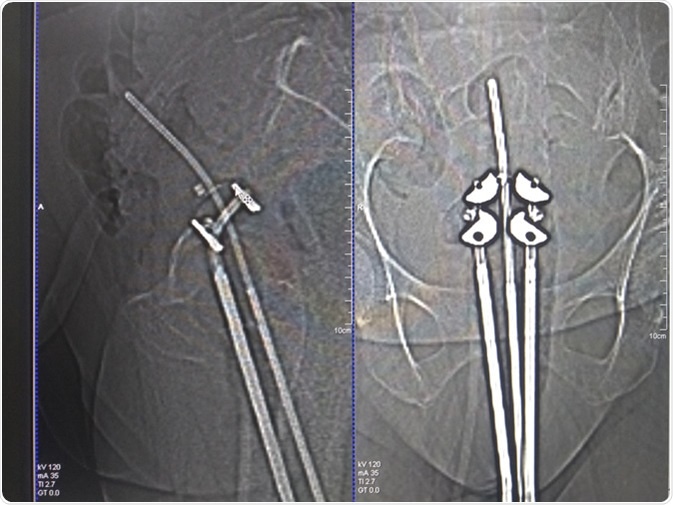

Brachytherapy applicator on CT scan. Image Credit: Chandrasekar28 / Shutterstock